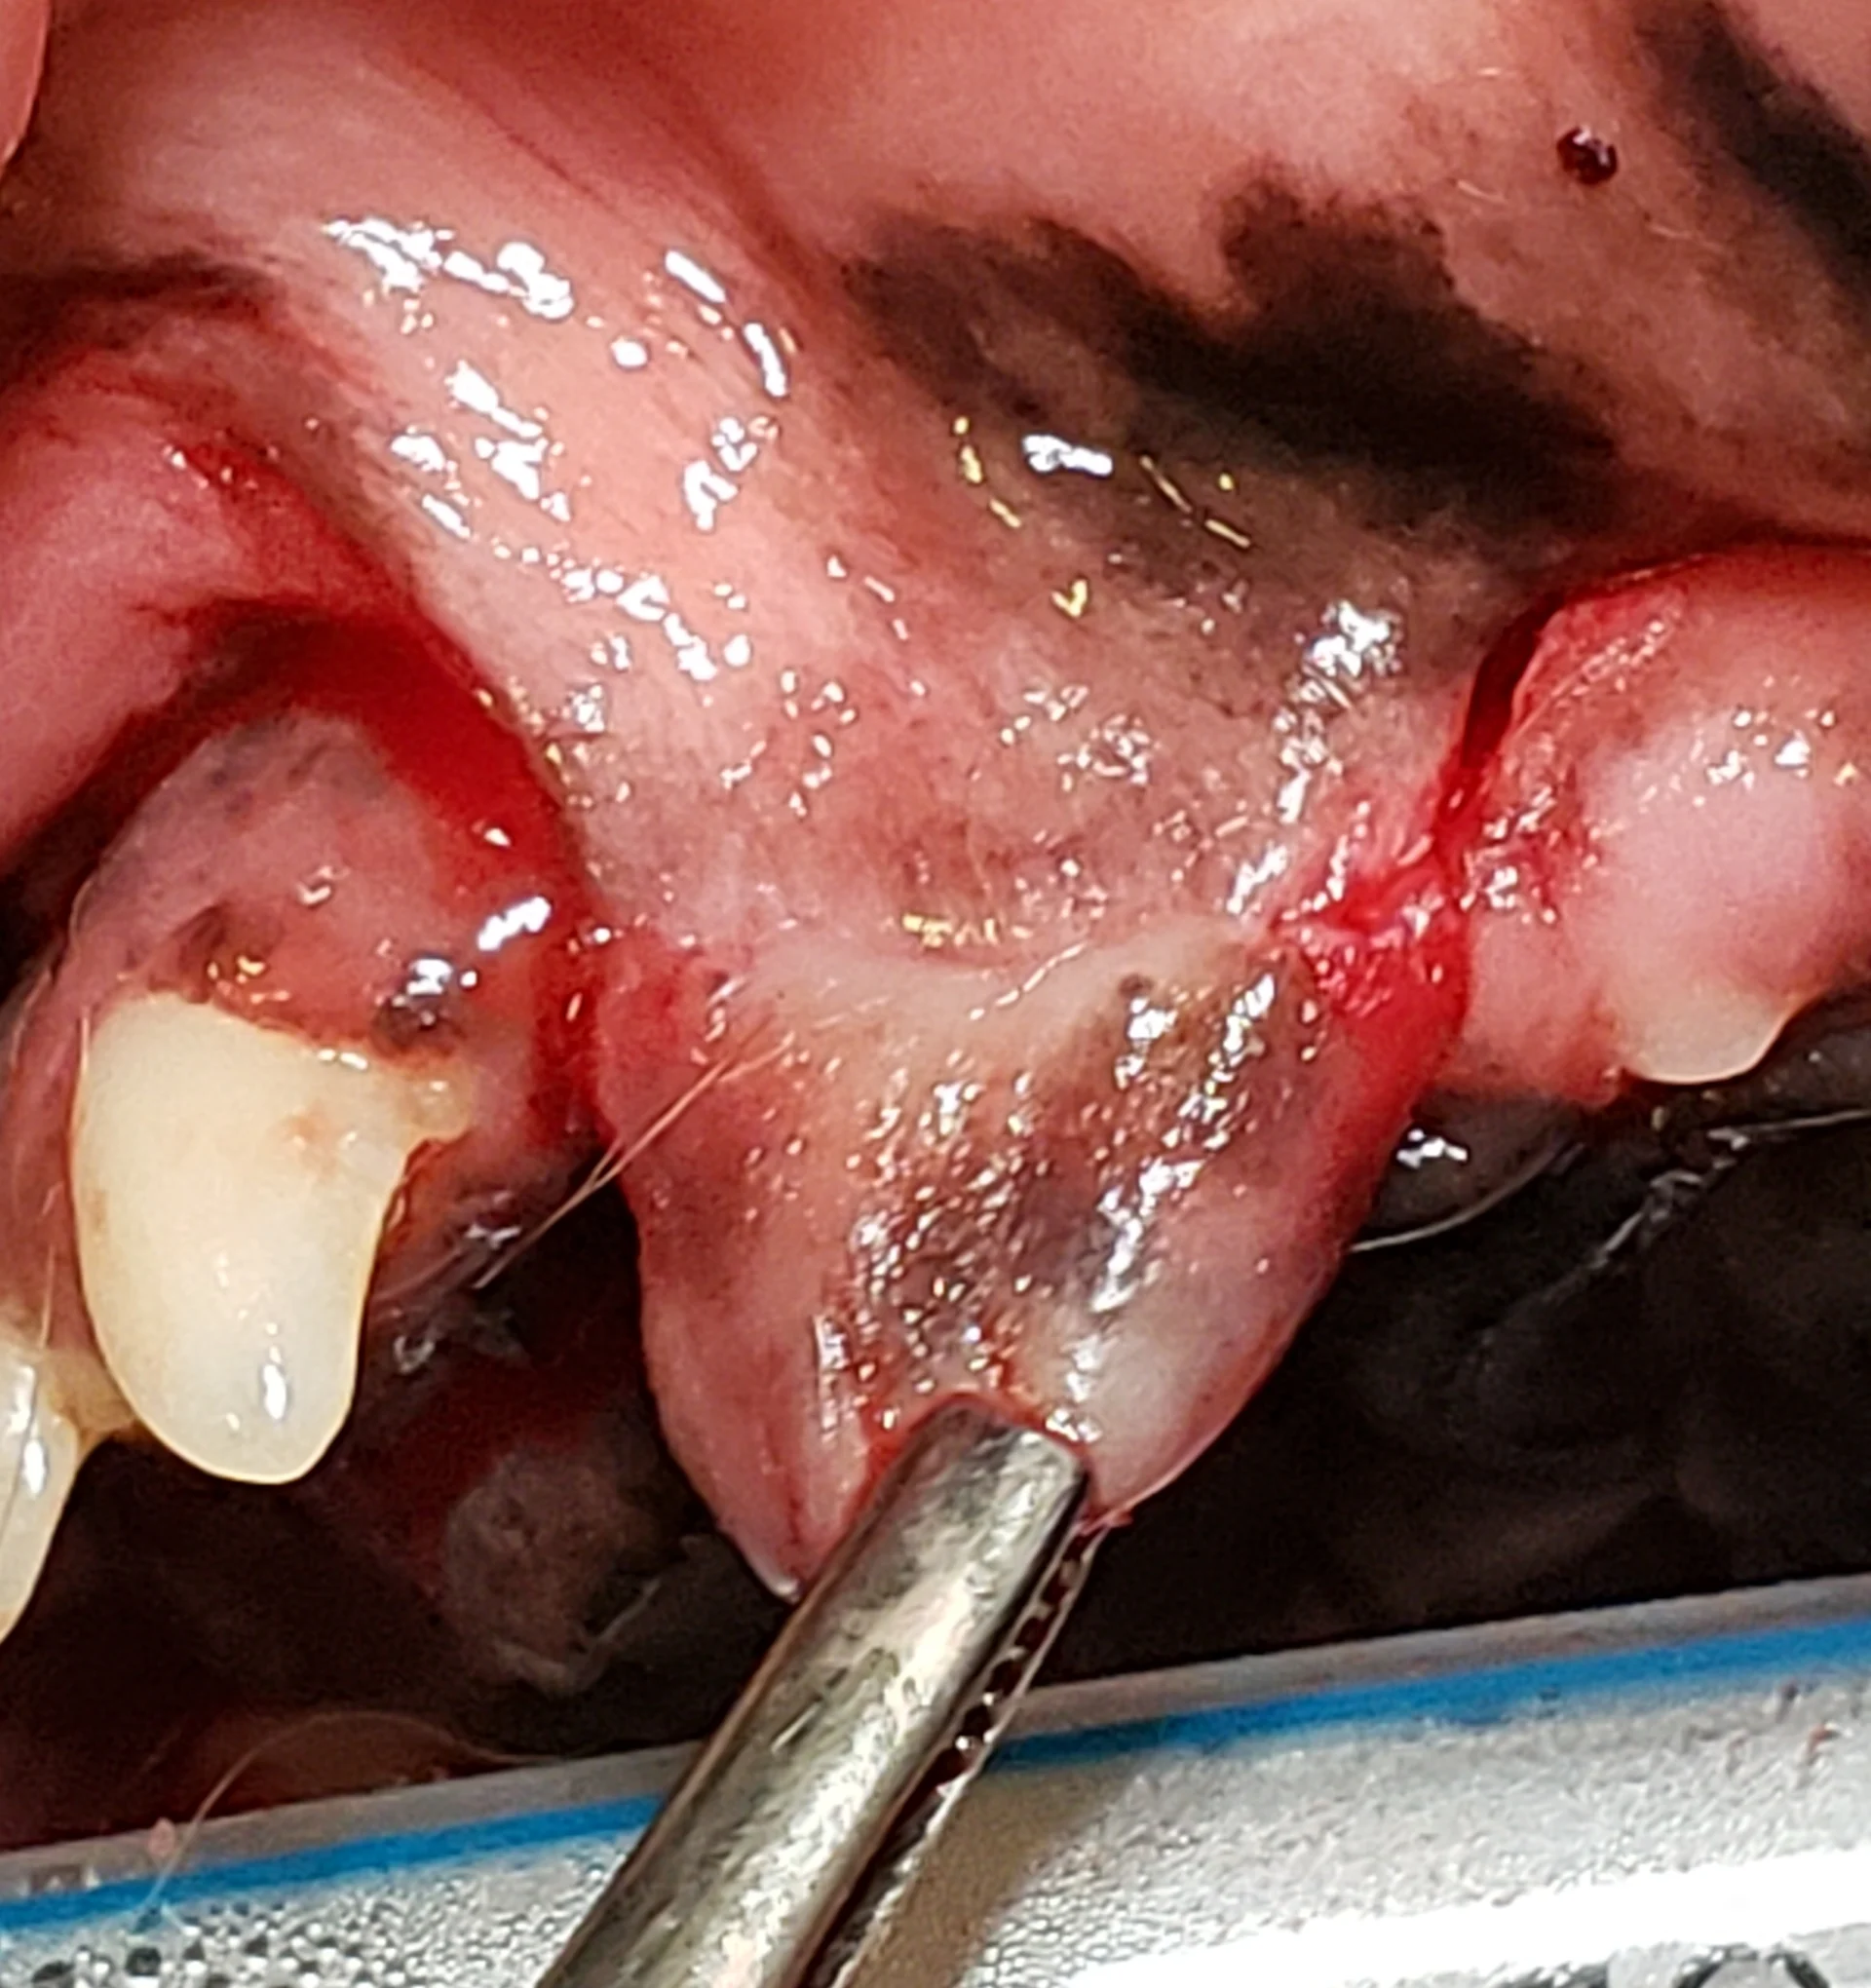

Step 4: Release Tension on the Flap

Provide additional tension release by carefully incising the thin layer of periosteum on the inner side of the flap using small, sharp scissors (eg, LaGrange, Goldman Fox) or a 15 or 15c scalpel blade.

Author Insight

This step can also be performed directly prior to close, but the author prefers to release tension at this point because soft tissue instruments are already in use. Care should be taken to not cut through the flap.